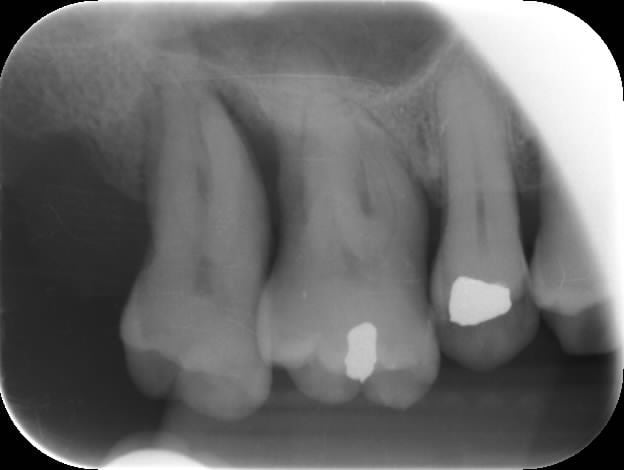

Dans la même veine des cas désespérés :

Patiente 70 ans

Hygiène déficiente malgré une séance de motivation, respiration buccale (bon elle passe les brossettes, elle me dit...la motivation a au moins servi à ça)

Vient consulter pour abcès paro répétés sur le secteur antérieur mandibulaire. A des sensibilités au froid sur la 16.

Financièrement impossible de faire du HN. ça tombe bien j'ai jamais fait de lambeau d'assainissement. J'ouvre de 33 à 43, surfaçage aux US finition manuelle, sutures suspendues. La patiente est contente, ça cicatrise assez rapidement, je suis surpris au vu de l'hygiène.

Ensuite on a parlé du secteur 3.

Ce que je ne comprends pas c'est que c'est asymptomatique pour elle. Moi je vois une mobilité stade 2 de la 37, le sondage qui plonge, évidemment.

J'ai prévenu la patiente qu'en ne faisant rien, on allait à l'extraction.

En faisant, on y va sûrement aussi mais vu qu'elle ne peut pas et ne pourra jamais faire d'implants, je lui ai dit qu'on pouvait tenter.

Pour moi la solution était d'extraire 37 et 38 en assainissant 36, et de prévoir une solution implantaire.

Financièrement, donc, pas possible et je ne me vois pas facturer un acte que je pense voué à l'échec. Comme j'ai du temps à perdre, j'ai fait un lambeau ce matin, de 34 à 38.

Ai-je une chance de cicatrisation ?

A quel moment décider d'extraire la 7 et la 8 pour sauver la 6 ?

Une telle lésion serait elle récupérable si bonne hygiène, furcation de 37 moins touchée et lésion moins apicale ?

P1 yt994f - Eugenol

3637 muyswe - Eugenol